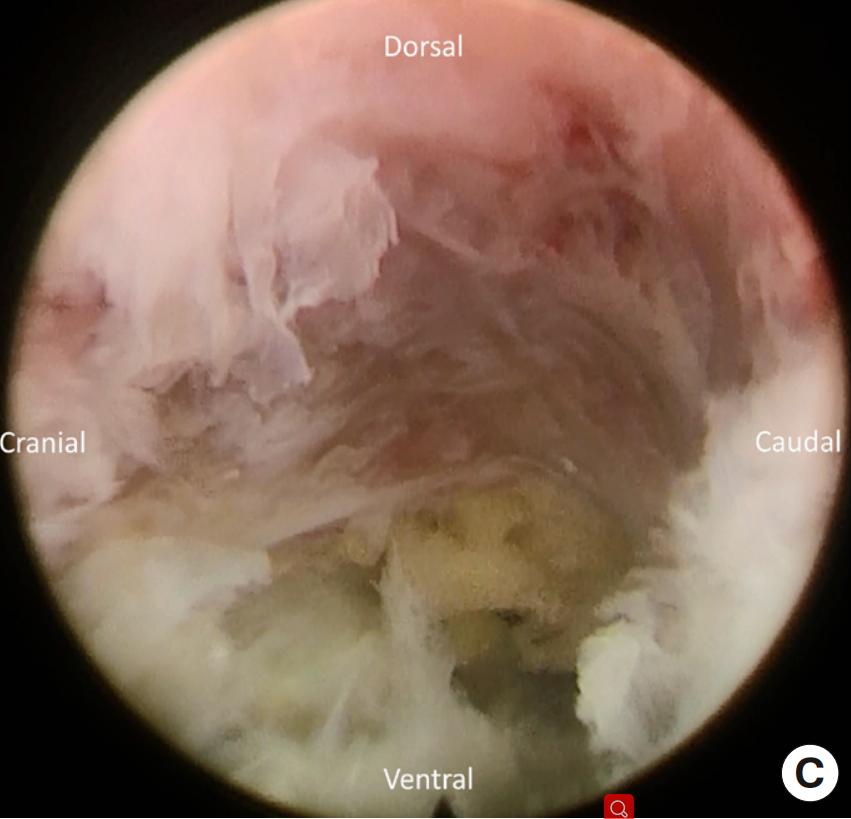

图3 :(A)镜下显示上关节突基部(B)椎间孔成形术中使用镜下磨钻(C)内镜下磨除上关节突的腹侧,扩大椎间孔

图4:(A)椎间孔成形术后显露突出的椎间盘(B)椎间盘切除术后显露走行根。